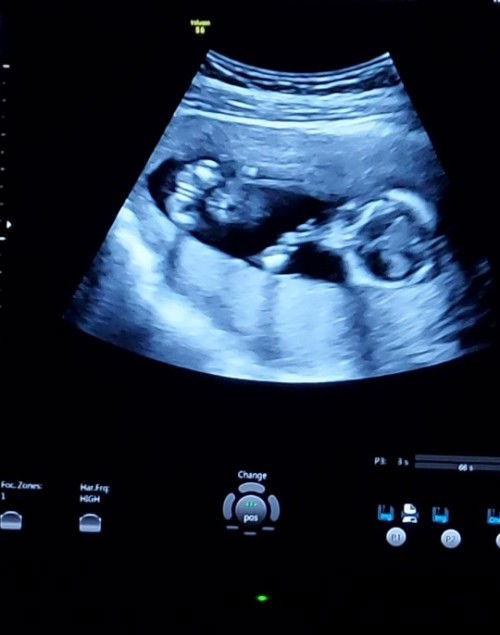

GENDER REVEAL??

it's a GIRL ?? Tama po ba ung nakita ko ? ๐๐๐๐ 14 weeks here! #firsttime_mommy

ayan po yung parang 3 layers na magkapatong. Kapag ganyan po Burger ang twag ng iba. Ibig sabihin girl po yan.

yes po its a girl dahil dun sa parang burger โบ๏ธ. Congrats po sana ako din girl na.